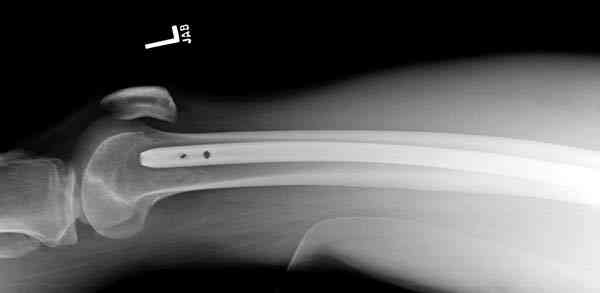

В приложении пример огнестрельного ранения бедра, оперированного на 2 сутки после ранения.

Штифтование было выполнено только на вторые сутки по причине задержки перевода из другого госпиталя, АБ профилактика была начата в другом учреждении, с момента госпитализации пациента к ним. Входное пулевое отверстие и зона введения штифта зажили первичным натяжением.

В конце 90-ых попалось несколько статей по nail exchange procedures in treatment of posttraumatic osteitis и решился попробовать на огнестрельных переломах, которые до этого лечил по полной схеме:расширенный дебрайдмент+ внешняя фиксации+промывные системы с антибиотиками и без антибиотиков в промывной среде. Всё заканчивалось длительной госпитализацией, плохими функциональными результатами( страдала функция колена), необходимостью повторной хирургией - отсроченная внутренняя фиксация переломов, длительной реабилитацией. На гвоздях процесс пошел лучше: остеомиэлитов не было и больные мобилизовывались быстрее.

Единственно что наблюдал - замедленная консолидация, судя по серийным Рг граммам. В приведенном случае прии вялом мозолееобразовании сделал ошибку, решившись динамизировать гвоздь - перелом сросся со значительным укорочением бедра - повторная хирургия по удлинению бедра и проксимальным запиранием, больной мобилизован и вполне доволен(кстати заметить больной с ВИЧ инфекцией - изначально скомпрометированный иммунитет и несмотря на это, всё прошло без костной и мягкотканной инфекции.